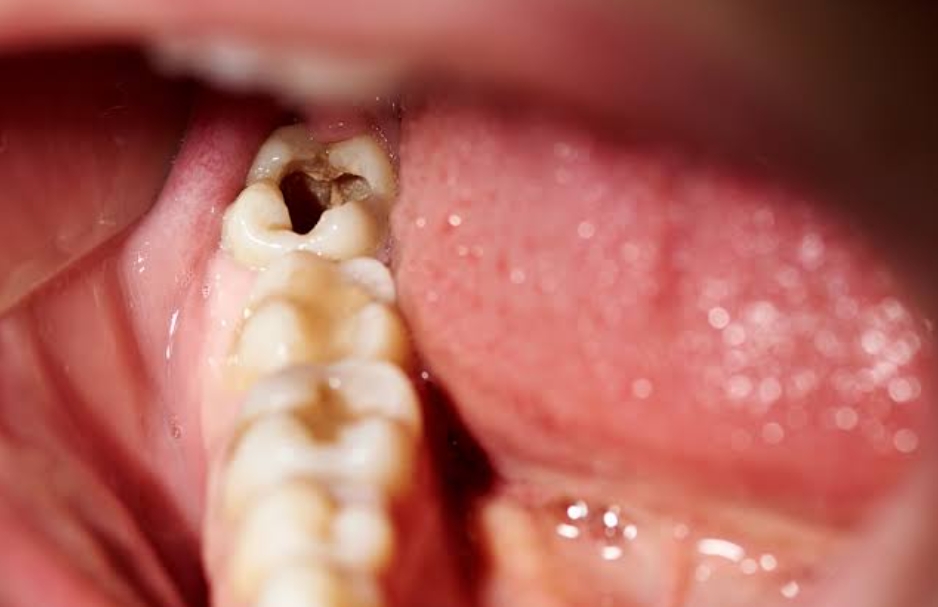

3. Stage Three: Dentin Decay – Sensitivity Becomes Noticeable

Once the decay breaks through the enamel, it reaches the dentin, the softer layer beneath. Dentin contains tiny tubes connected to the nerve of the tooth, which is why sensitivity increases at this stage.

- Noticeable cavity or hole in the tooth

Dentin decay progresses faster than enamel decay because dentin is much softer. Immediate treatment is essential. Your dentist will recommend larger fillings or possibly a dental crown, depending on how deep the damage is. Delaying treatment can allow bacteria to reach the pulp, causing severe pain and possible infection.